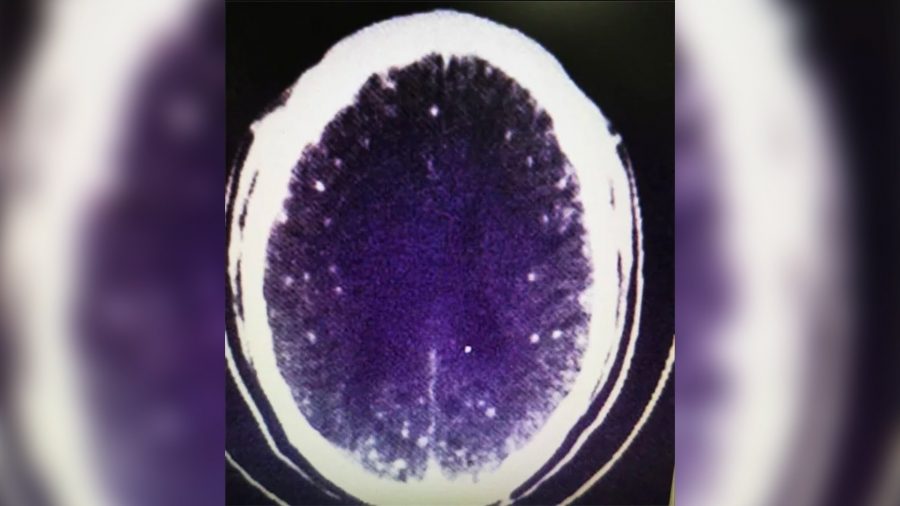

Une mère atteinte de la maladie d’Alzheimer, ne reconnaissant pas son fils, retrouve la mémoire grâce à un régime alimentaire spécial pour le cerveau